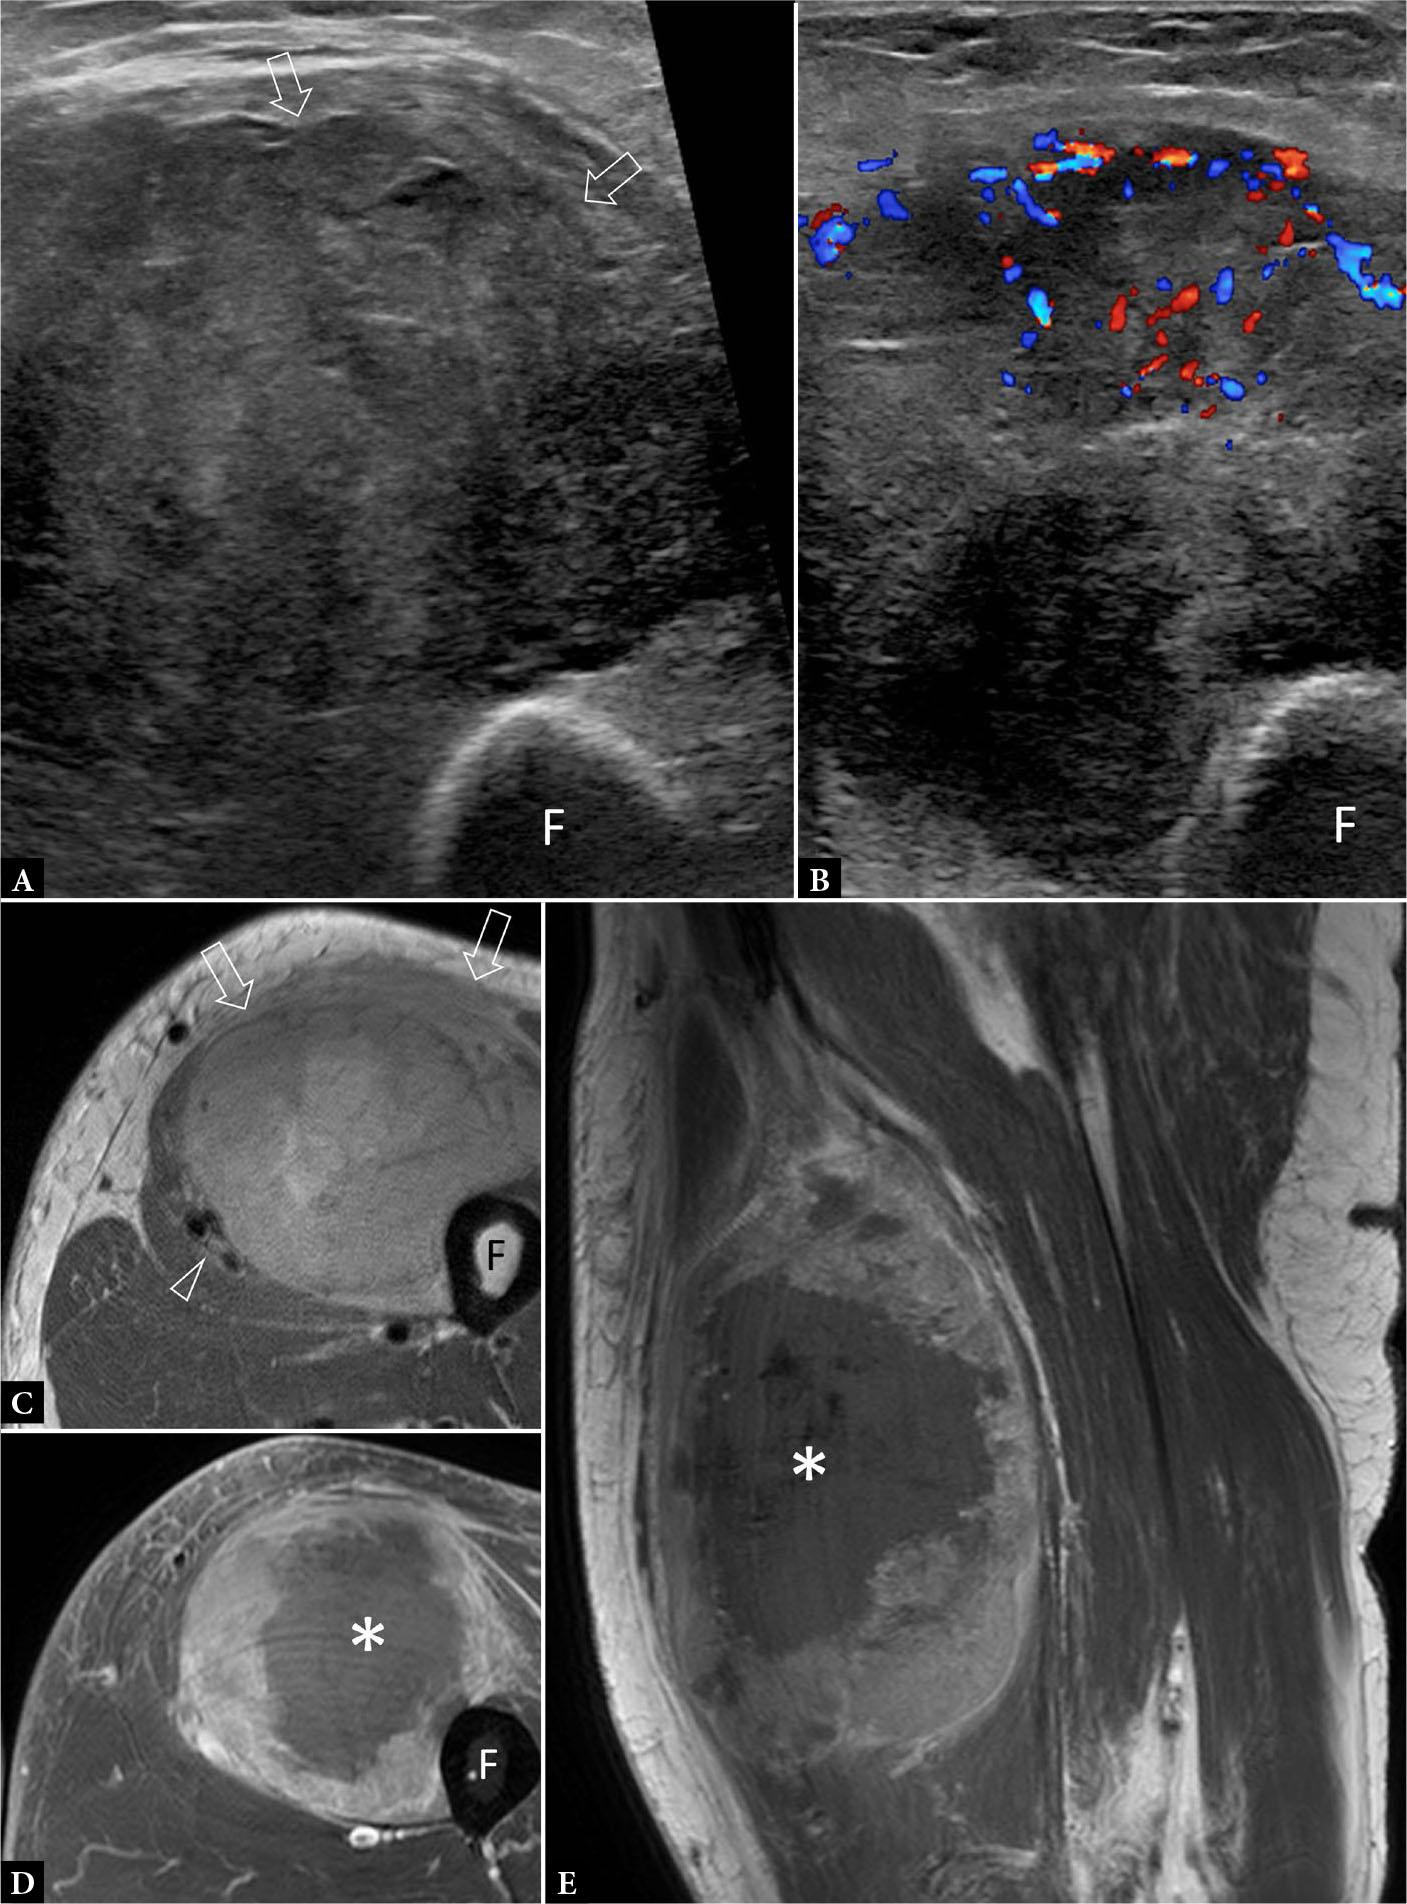

Fig. 1.

63-year-old male with enlarging thigh mass for five months. Transverse A. greyscale and B. color Doppler ultrasound show large moderately hyperemic mass (arrows) partially encasing the femoral (F) cortex. The large size, rapid growth, and moderate hyperemia make sarcoma most likely. No necrosis is evident. C. Axial proton-density weighted image shows that the tumor contacts, but does not infiltrate, the femoral cortex. The femoral neurovascular bundle (NVB) is also not infiltrated (arrowhead). T1-weighed fat-saturated post-contrast D. axial and E. sagittal images show that the central tumor area (*) is non-enhancing, compatible with necrosis. The necrosis cannot be appreciated on ultrasound A., B. Percutaneous biopsy of the tumor margins revealed a pleomorphic rhabdomyosarcoma